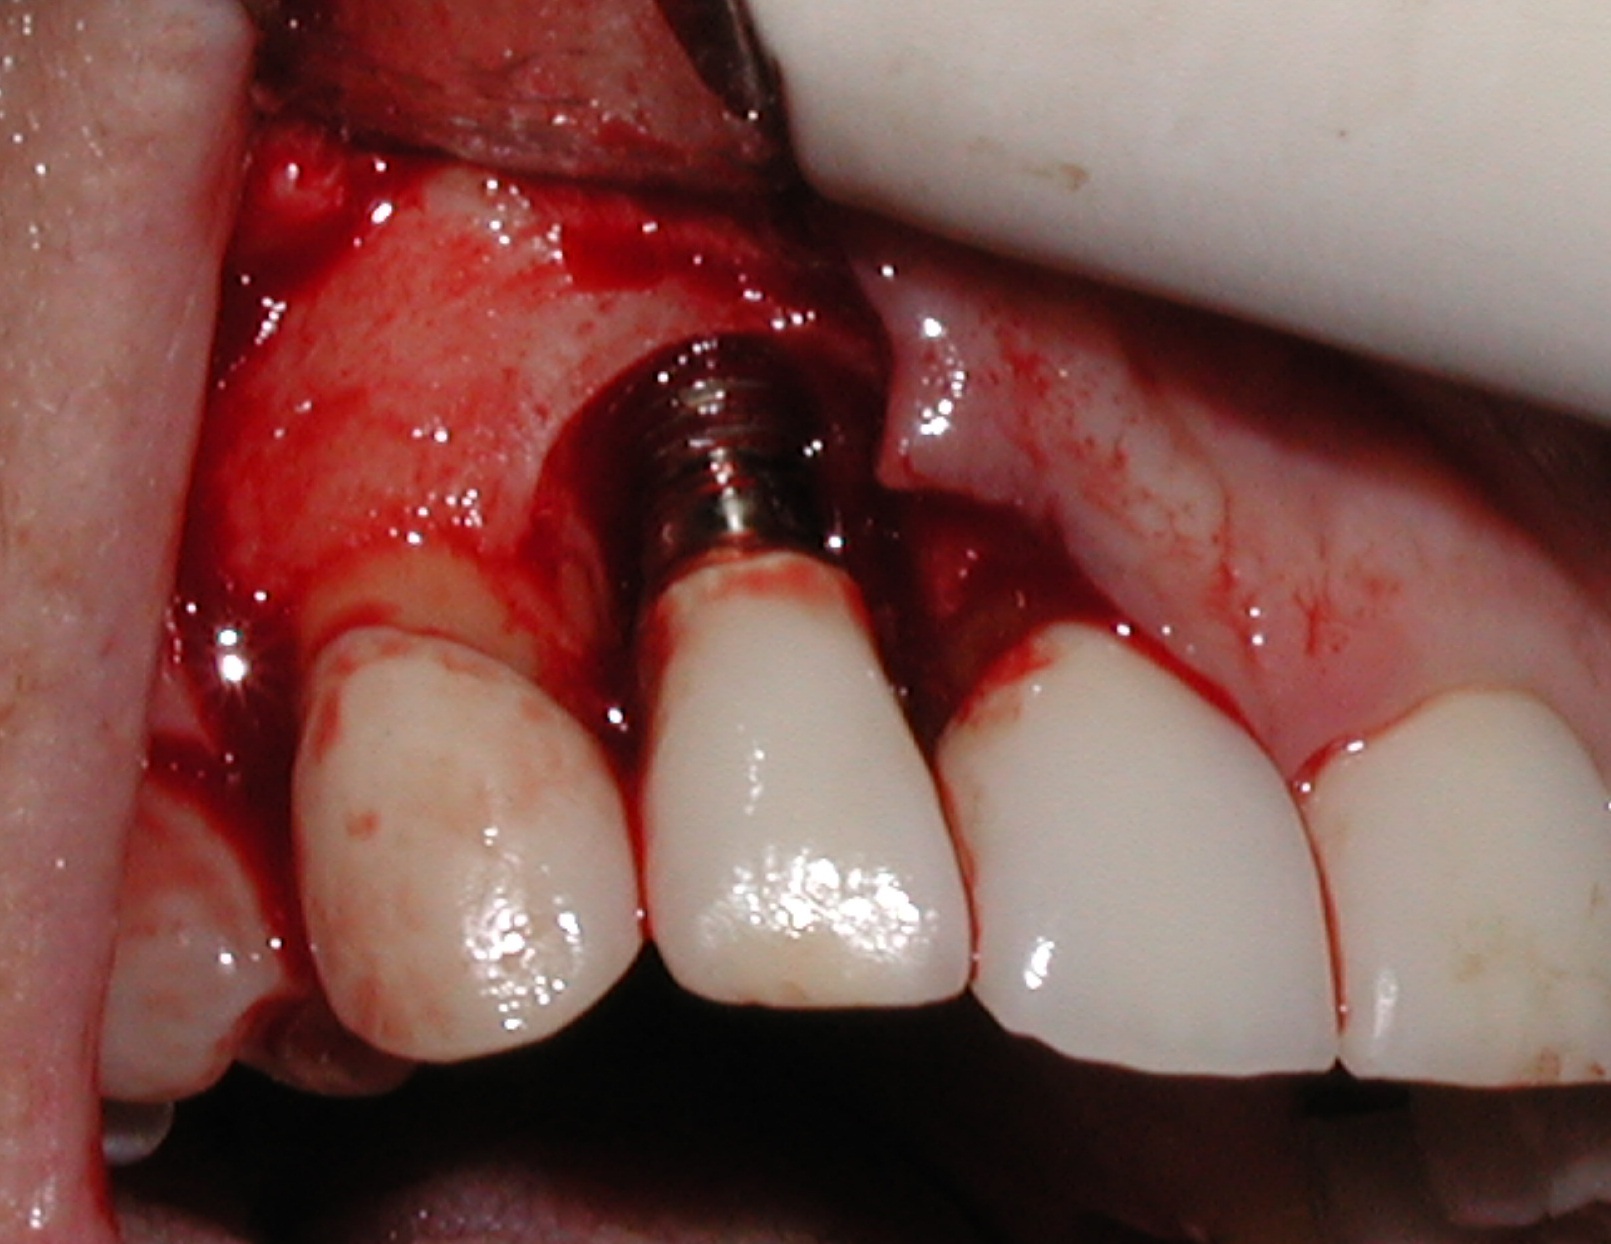

Fig 6. Clinical health of tissue 6 years post-repair (2014).

Figure 6